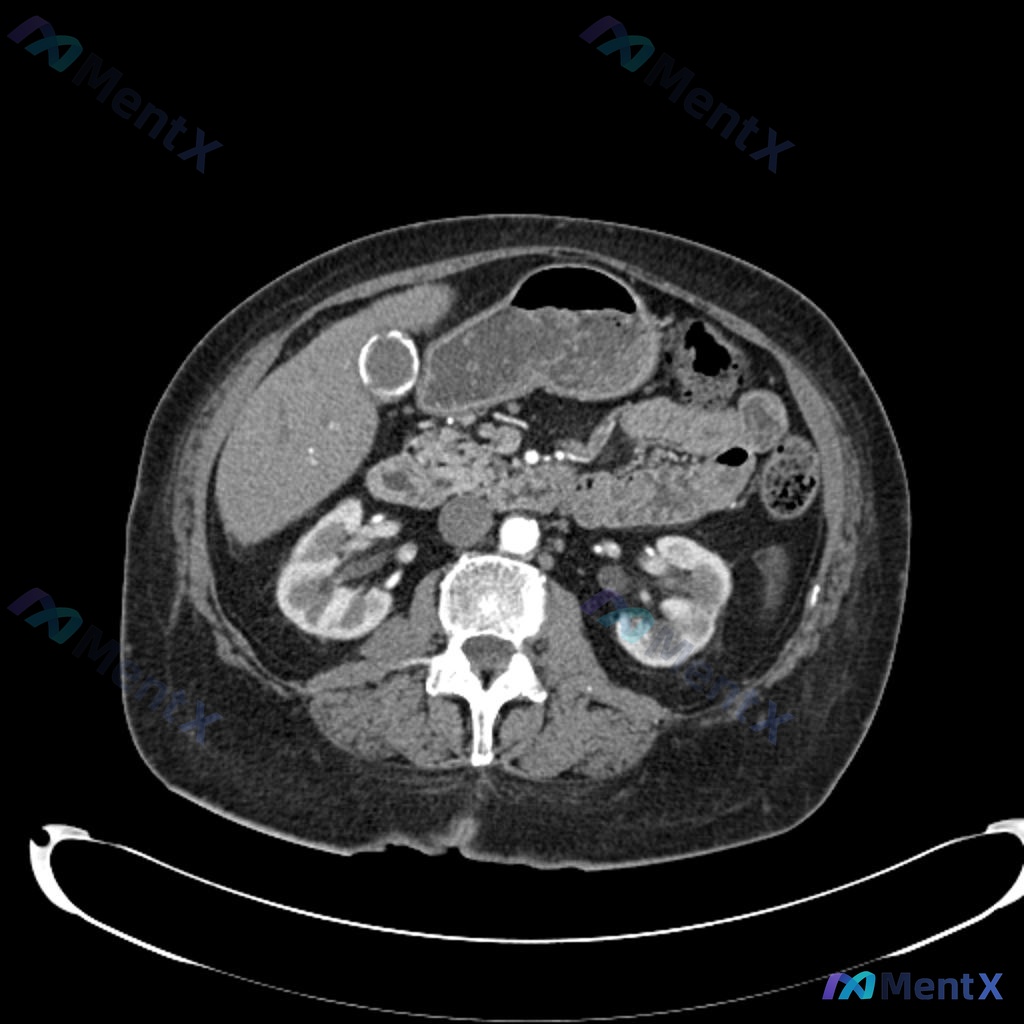

整理了一个非常考验急诊决策思维的病例,稍有不慎就容易被「显眼」的影像发现带偏。 --- 病例基本情况 44岁女性,因低速追尾事故送急诊。 - 受伤时系了安全带 - 主诉:颈部僵硬 + 安全带部位左下腹疼痛 - 生命体征完全平稳:T37.1℃,BP117/68mmHg,P72次/分,R13次/分,Sp...